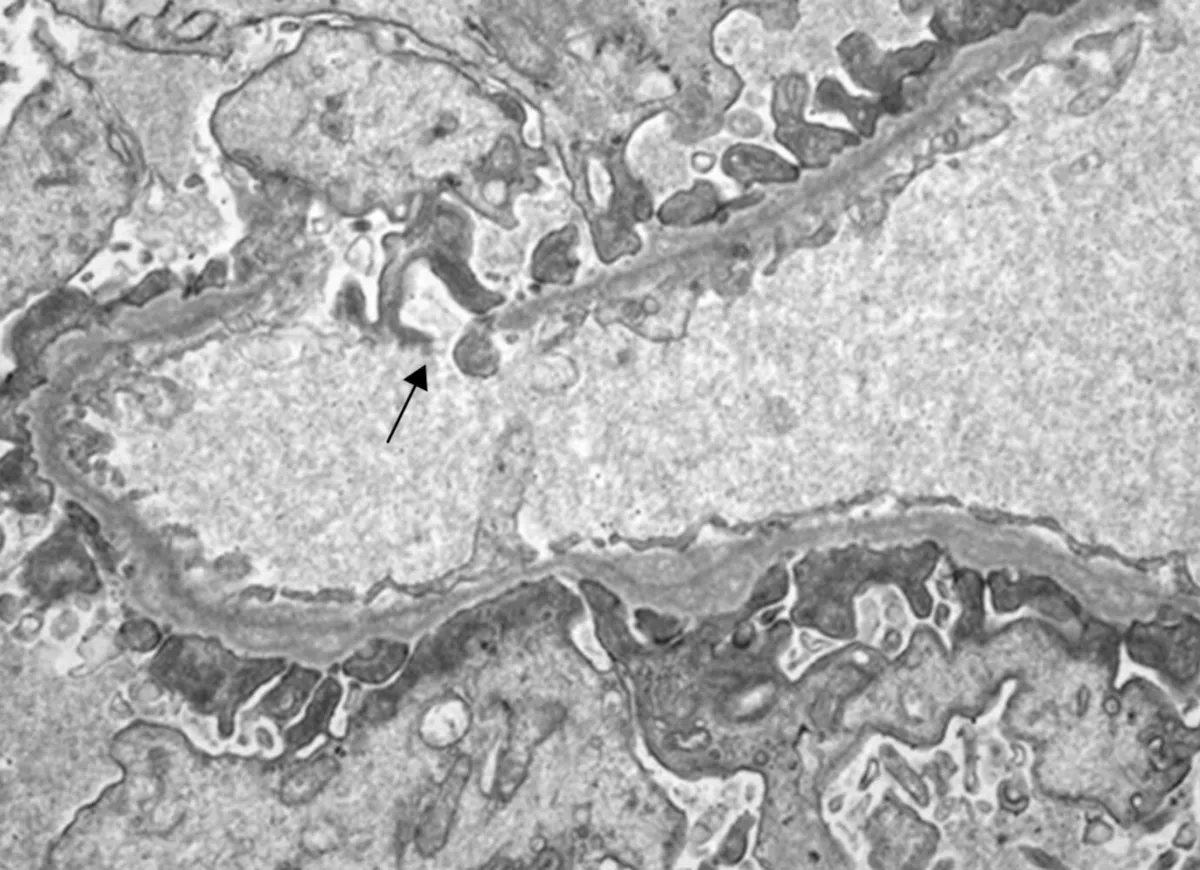

Como investigar a Membrano proliferativa de forma prática?

Como investigar a Membrano proliferativa de forma prática?Desvende a membranoproliferativa! Aprenda estratégias práticas e objetivas para investigar essa glomerulopatia desafiadora, otimizando diagnósticos e tratamentos na nefrologia.

Luís Sette

2 anos atrás